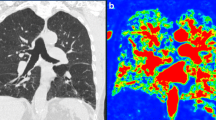

HRCT scans were acquired on a Siemens Sensation 64-slice CT (Siemens, Erlangen, Germany) from the apices to the costophrenic angles at full inspiration at 120 kVp and 130 mAs. All patients were scanned in the supine position. Contiguous slices were reconstructed at 1-mm slice thickness with a 0.5-mm increment and a 512 × 512 matrix. Automatic tube current modulation was utilised for all patients. Images were reconstructed using lung windows (window width 1,500, centre -700). Images were transferred to a workstation and analysed using quantitative lung analysis software (Pulmo3D, Syngo Via, Siemens, Erlangen, Germany) for calculation of total lung capacity, mean lung density, and the total low attenuation value % (LAV%) of the lungs. For the LAV% an established threshold of -950 HU was used to indicate emphysema [16].

All patients with CPFE were subjectively correctly identified on LGE-MRI. Figures 2 and 3 provide imaging examples in two patients with CPFE of LGE in regions of pulmonary fibrosis in the lower lobes and an absence of LGE in regions of emphysema in the upper lobes. The contrast-to-noise ratio was 30.1. Table 2 shows the median SI in regions of fibrosis and emphysema. Qualitatively, emphysema showed no evidence of LGE-MRI enhancement in any patient. Quantitatively, significant differences were found in median SI in regions of fibrosis compared to regions of emphysema (25.8, IQR 18.4–31.0 versus 5.3, IQR 5.0–8.1, p < 0.001). ROC analysis of SI in fibrotic areas in the lower lobes compared to emphysematous areas in the upper lobes in CPFE patients showed an area under the curve of 0.95, p < 0.0001. Using a SI value of ≥ 12 resulted in a sensitivity of 95% and specificity of 100% in differentiating fibrosis from emphysema in CPFE patients (Fig. 4). The percentage of SI increase in pulmonary fibrosis compared to emphysema was 278.5% while the percentage of density increase in pulmonary fibrosis compared to emphysema on HRCT was 36.4%. Significant differences were seen between LGE-MRI and HRCT in the extent of reticulation (12.5, IQR 5.0–20.0 versus 15.0–26.3, IQR 5–40, p = 0.038) and honeycombing (5.0, IQR 0.0–10.0 versus 20.0, IQR 10.6–20.0, p = 0.001) but not in traction bronchiectasis (10.0, IQR 5–15 versus 15.0, IQR 5.0–15, p = 0.878 (Table 3).